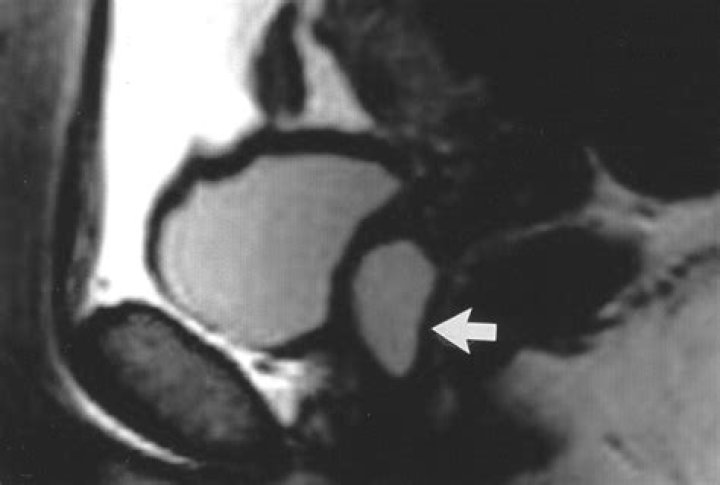

Paraurethral Cyst Paraurethral cysts, also known as Skene’s glands, are found in the wall of the vagina near the urethra. In a newborn, Skene’s duct can become blocked by a large cyst filled with hormone secretions. Sometimes the cyst may close off the urethral opening.